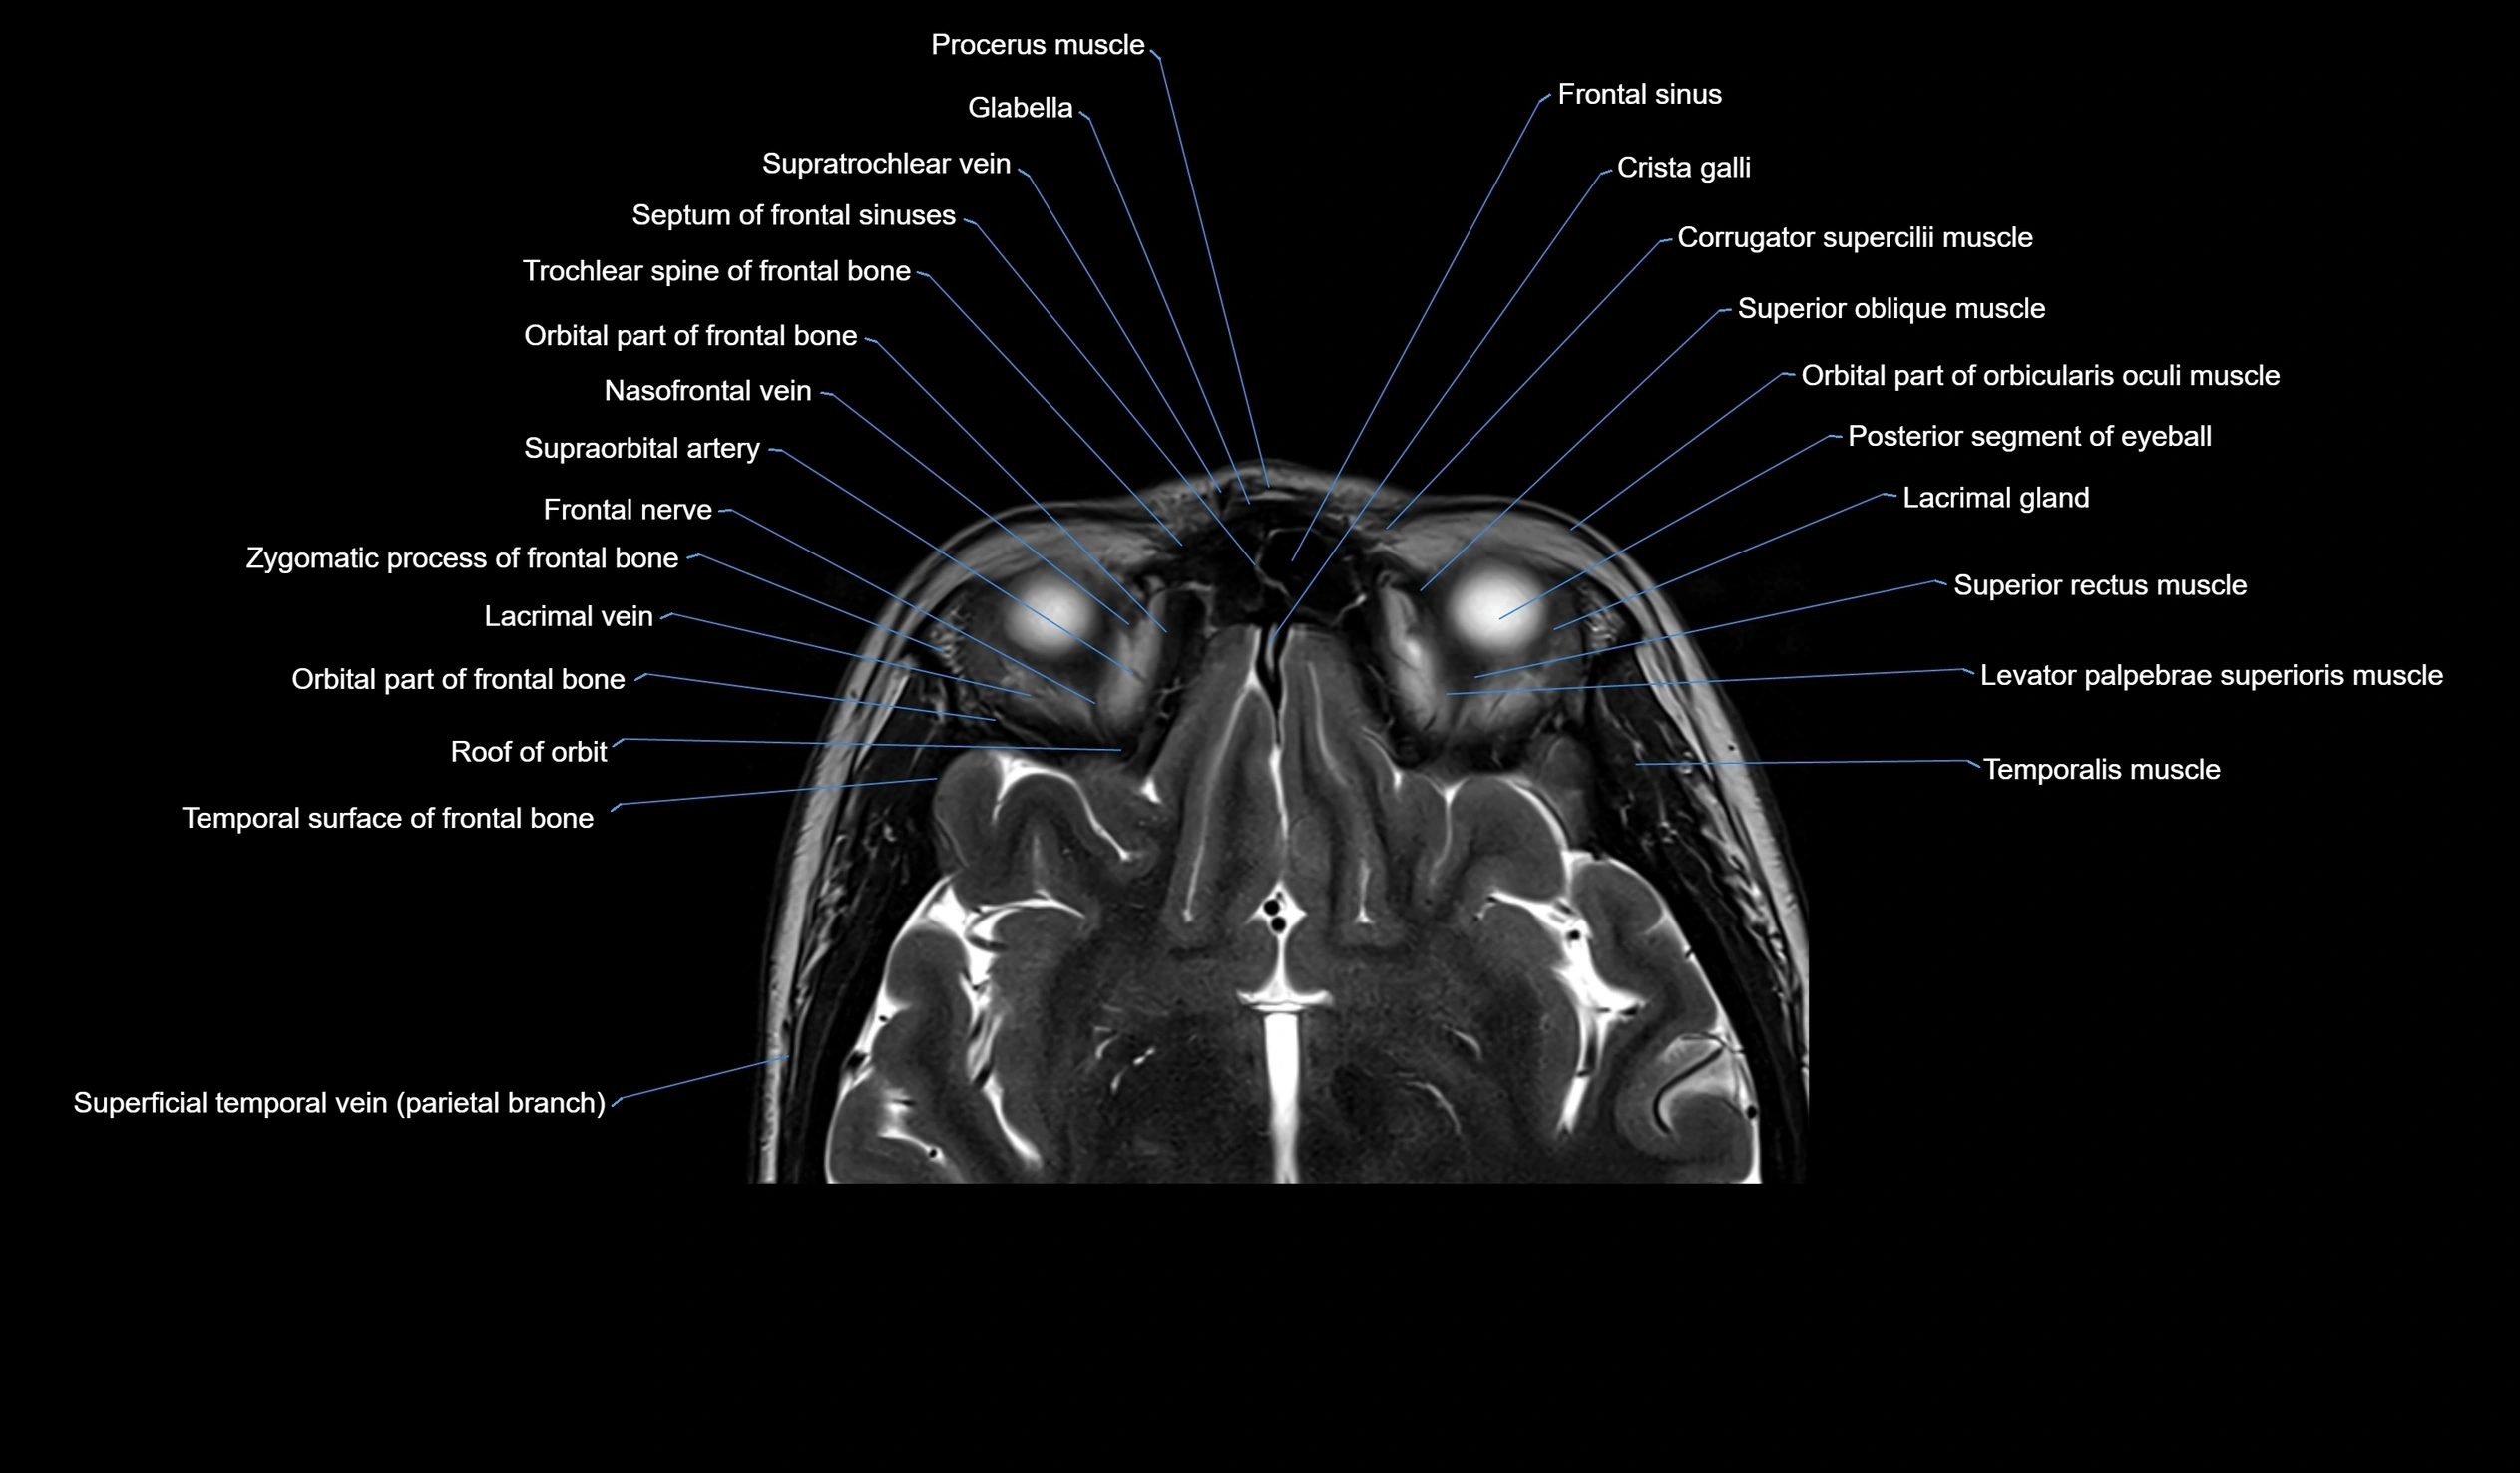

MRI images